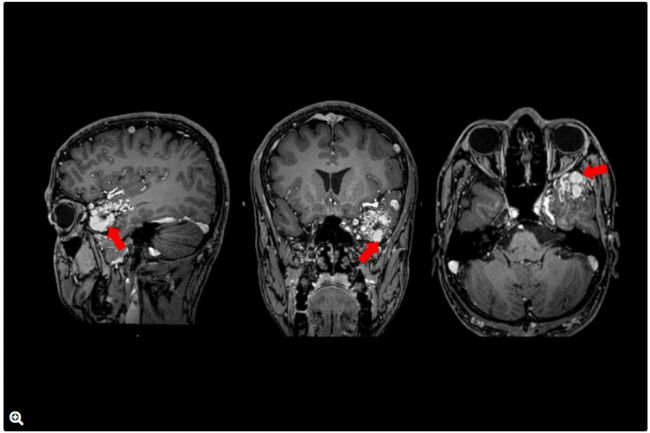

4.術后

圖9:T1加權MRI圖像,顯示AVM病灶完全切除(紅色箭頭)。

圖11:術后腦血管造影:AP投影顯示無

早期引流靜脈或殘余AVM(紅色箭頭)。

圖12:術后腦血管造影:側位投影顯示無早期引流靜脈或殘余AVM。